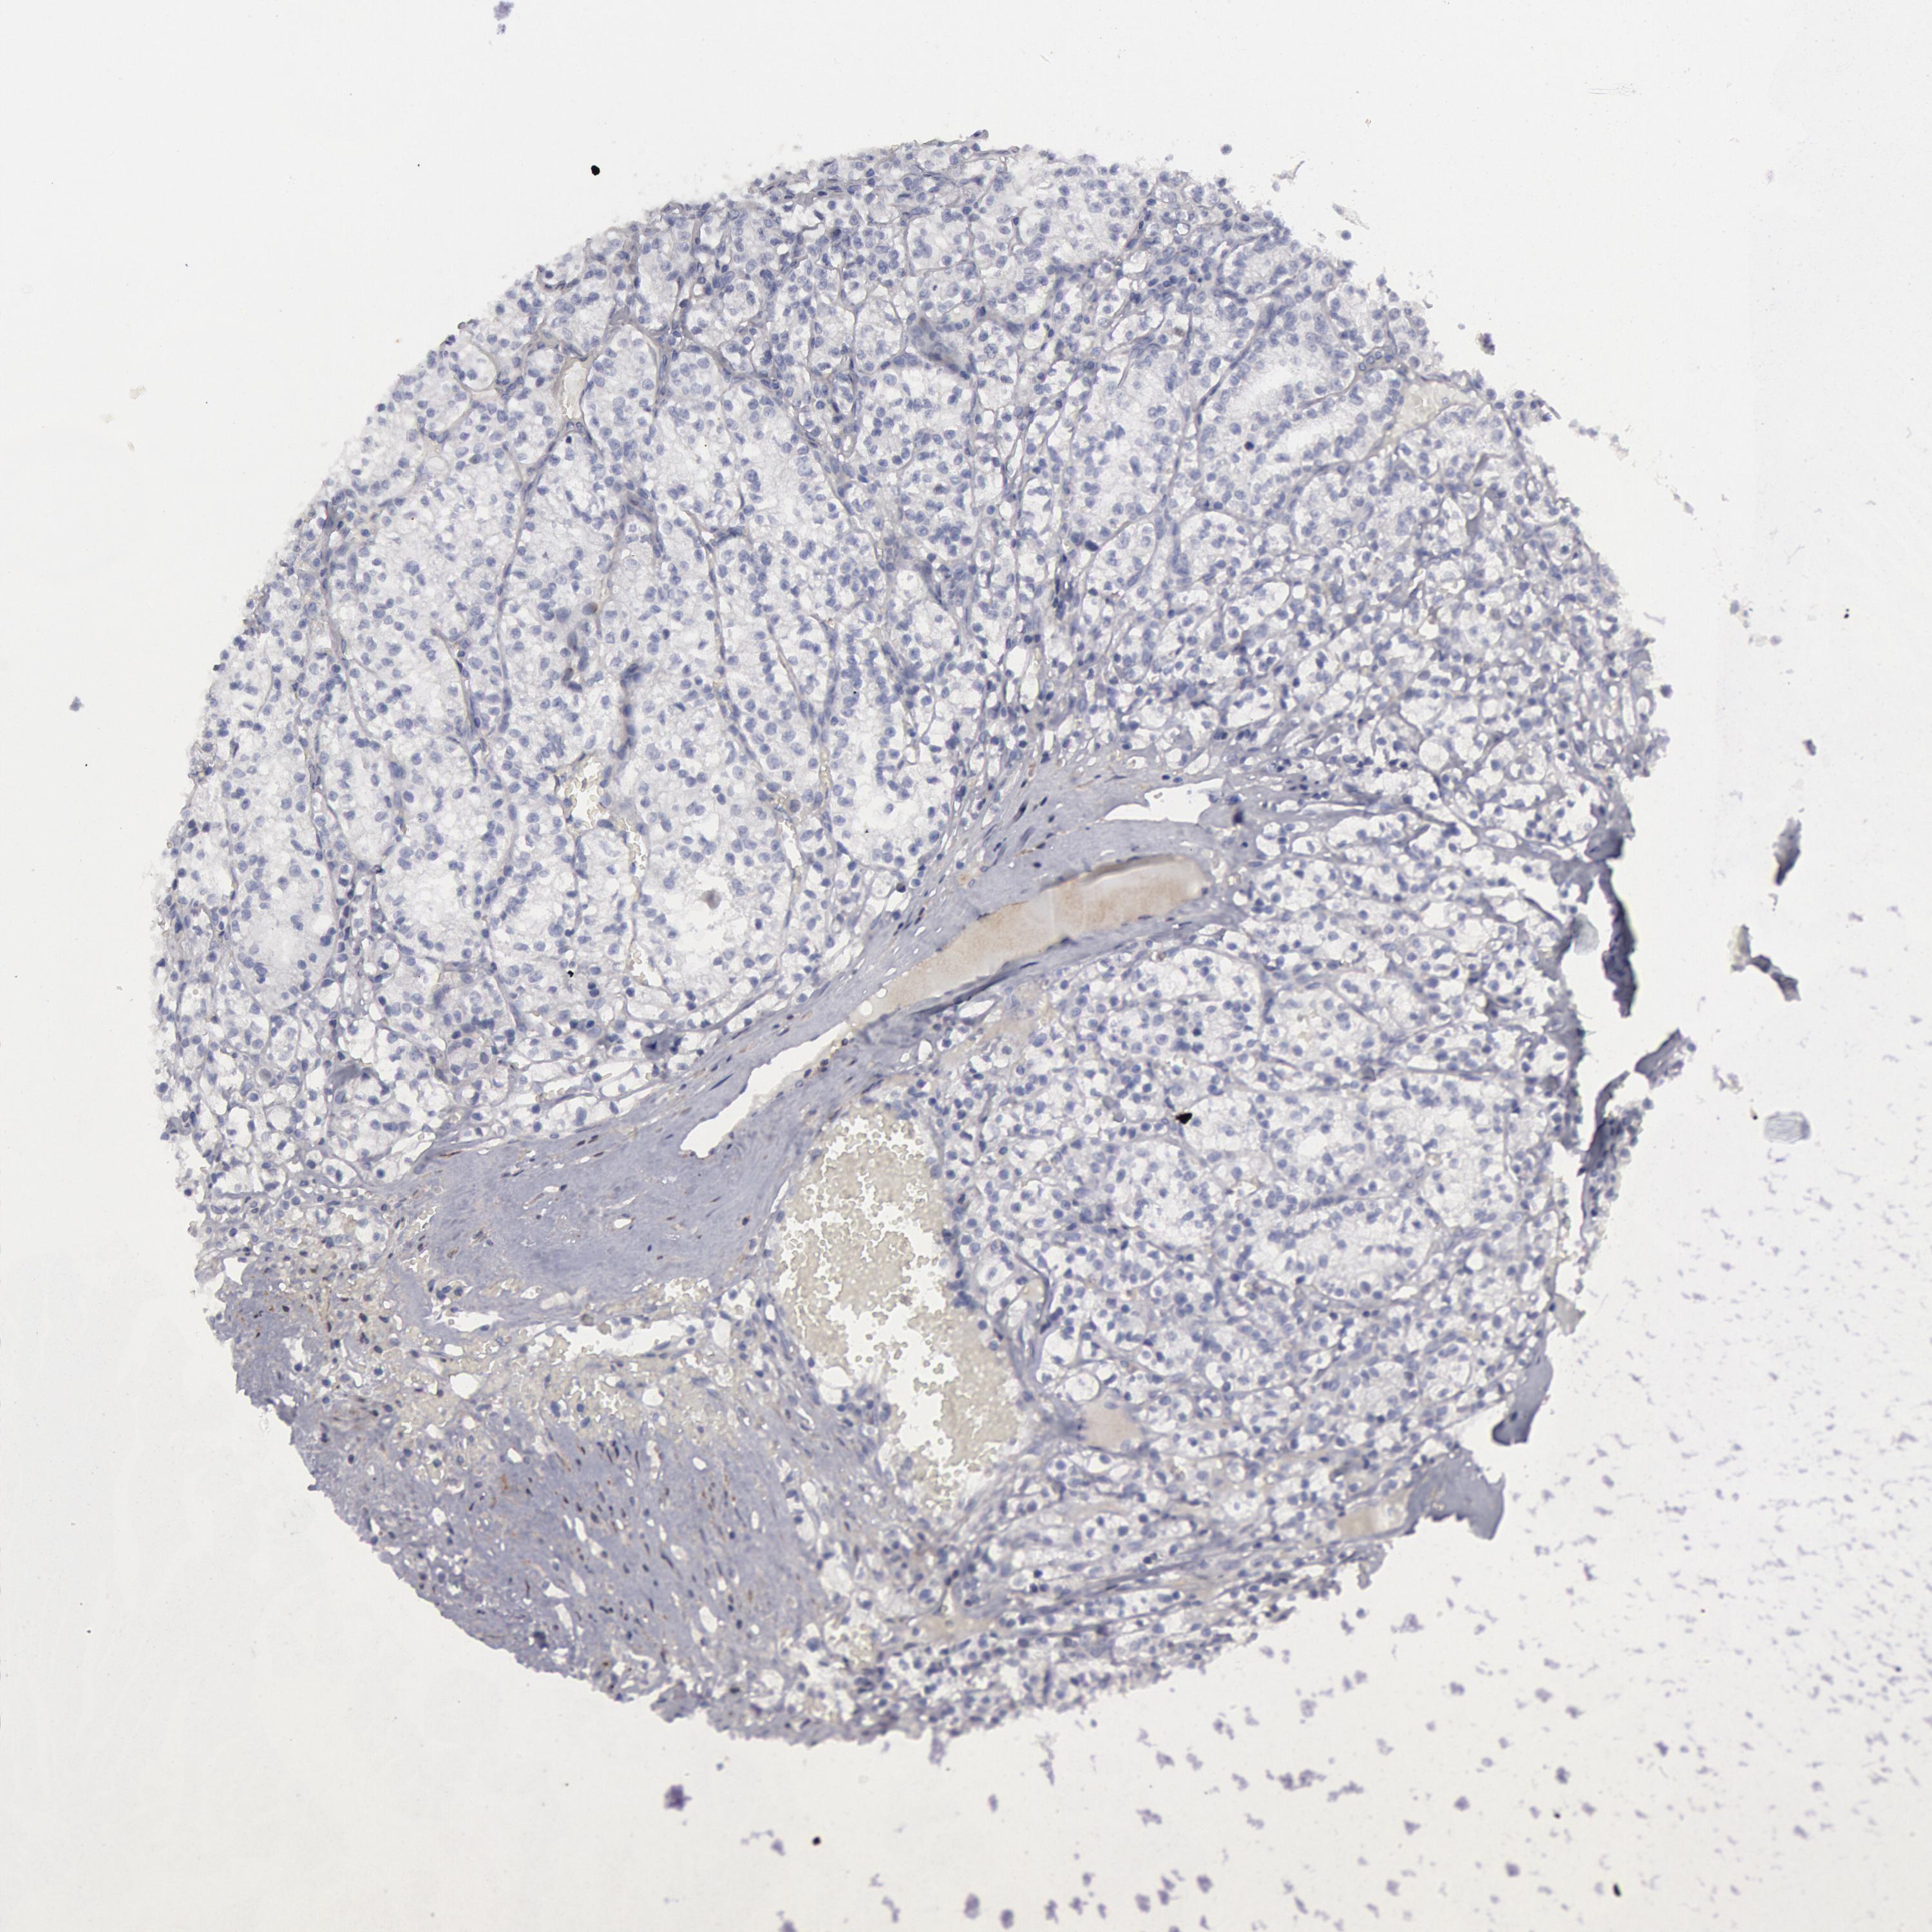

KIDNEY RENAL PAPILLARY CELL CARCINOMA (TCGA) - Interactive survival scatter ploti

The Survival Scatter plot shows the clinical status (i.e. dead or alive) for all individuals in the patient cohort, based on the same data that underlies the corresponding Kaplan-Meier plots. Patients that are alive at last time for follow-up are shown in blue and patients who have died during the study are shown in red.

The x-axis shows the expression levels (FPKM) of the investigated gene in the tumor tissue at the time of diagnosis. The y-axis shows the follow-up time after diagnosis (years). Both axes are complimented with kernel density curves demonstrating the data density over the axes. The top density plot shows the expression levels (FPKM) distribution among dead (red) and alive patients (blue). The right density plot shows the data density of the survived years of dead patients with high and low expression levels respectively, stratified using the cutoff indicated by the vertical dashed line through the Survival Scatter plot. This cutoff is automatically defined based on the FPKM cutoff that minimizes the p-score. The cutoff can be changed by dragging the vertical line or by entering a cutoff value in the square labeled "Current cut-off".

Under the Survival Scatter plot the p-score landscape (black curve; left axis) is shown together with dead median separation (red curve; right axis). Dead median separation is the difference in median mRNA expression between patients who have died with high and low expression, respectively. It is calculated as follows: median FPKM expression of dead patients with high expression - median FPKM expression of dead patients with low expression. This is intended to aid the user in visually exploring custom cutoffs and the associated p-scores and dead median separation.

Individual patient data is displayed and can be filtered by clicking on one or more of the category buttons on the top of the page. Categories describing expression level and patient information include: high, low, alive, dead, female, male and tumor stages. The scale of the x-axis can be toggled between linear and log-scale by clicking on the "x log" button. Mouse-over function shows TCGA ID, patient information and mRNA expression (FPKM) for each patient.

& Survival analysisi

Kaplan-Meier plots summarize results from analysis of correlation between mRNA expression level and patient survival. Patients were divided based on level of expression into one of the two groups "low" (under cut off) or "high" (over cut off). X-axis shows time for survival (years) and y-axis shows the probability of survival, where 1.0 corresponds to 100 percent.

FLOT1 is not prognostic in Kidney Renal Papillary Cell Carcinoma (TCGA)